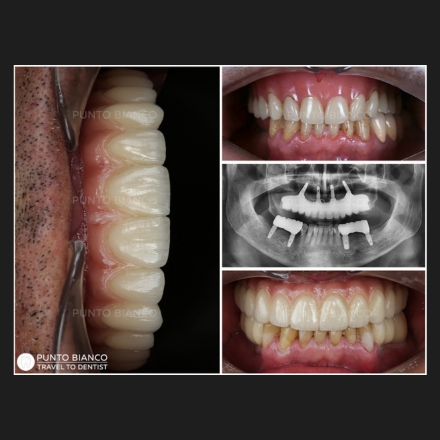

Recomand cu căldură această clinică din mai multe motive. În primul rând, pentru profesionalismul demonstrat de întregul personal pe parcursul întâlnirilor la clinică. În al doilea rând, pentru curățenia exemplară pe care personal nu am văzut-o la nicio altă clinică. În al treilea rând, pentru echipamentele de ultimă generație disponibile în clinică și, în special, pentru faptul că această clinică nu refuză pacienții cu cazuri extrem de complicate, așa cum a fost cazul meu. Am încercat să găsesc o clinică dentară în Canada, țara în care locuiesc din 2000. Am aflat că am nevoie absolută de un chirurg maxilo-facial. Am fost refuzat. Am trimis scanarea mea 3D în diferite țări, cum ar fi Ungaria, România, Turcia. Multe clinici, când au văzut scanarea mea 3D, au încetat să comunice cu mine prin email. Singurii care au comunicat cu mine, care mi-au răspuns la fiecare întrebare și îngrijorare, au fost cei de la Clinica Punto Bianco.